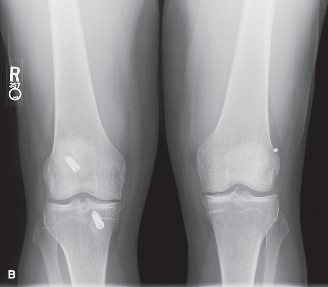

Standard radiographic evaluation of the knee is the first-line imaging modality for anterior knee pain. The patient's initial X-rays (Figures 9-1 A-C) include a weight-bearing anteroposterior (AP), a true lateral at 30 degrees of flexion, and an axial (Merchant or Sunrise) view.

The AP view demonstrates normal tibiofemoral joint spaces with no evidence of osteochondral lesions, loose bodies, or degenerative changes. The lateral view is scrutinized for patellar height. The Insall-Salvati ratio (the ratio of the patellar tendon length to the greatest diagonal length of the patella) is calculated at 1.05, which falls within the normal range (0.8 to 1.2), ruling out patella alta or baja. The lateral view also shows no evidence of trochlear dysplasia; the crossing sign is absent, and the trochlear bump is not prominent.

The Merchant view is arguably the most critical radiograph for this patient. It reveals a subtle lateral tilt of the patella and mild lateral subluxation. The sulcus angle measures 138 degrees (normal is typically <145 degrees), indicating adequate trochlear depth. However, the congruence angle is slightly lateralized, confirming the clinical suspicion of lateral patellar maltracking. There is no evidence of advanced patellofemoral osteoarthritis, osteophyte formation, or subchondral sclerosis.